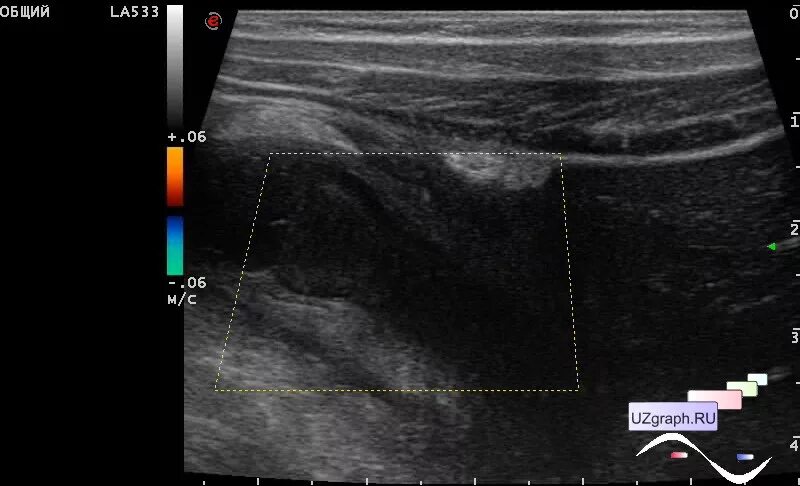

Аппендицит на узи можно ли